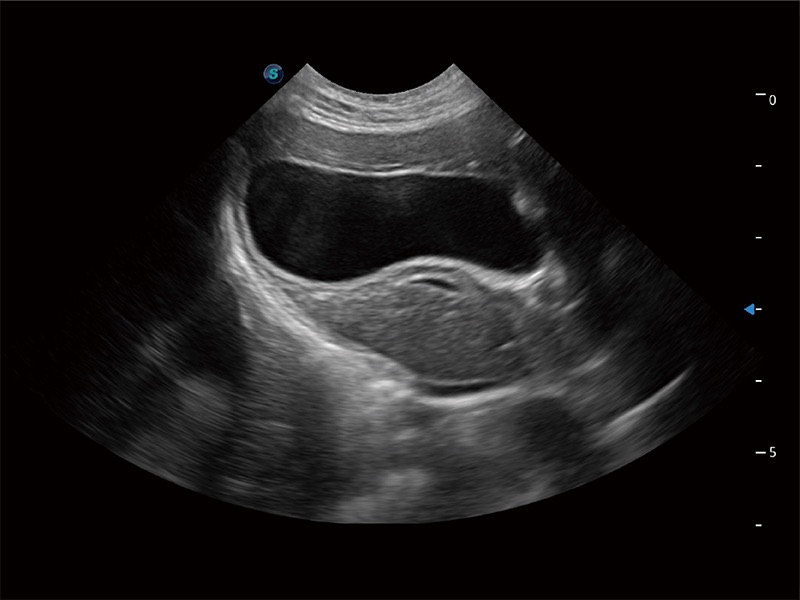

Klinisches Vertrauen verlangt hohe Leistung und fortschrittliche Werkzeuge. ProPet wurde für abdominelle und oberflächliche Untersuchungen mit fortschrittlichen Werkzeugen entwickelt, die Tierärzten in der täglichen klinischen Praxis helfen wie nie zuvor.

Das ProPet wurde für Tierärzte entwickelt, um ein sehr hohes Maß an Professionalität bei allen tierärztlichen Anwendungen sicherzustellen. Mit der auf den Tierarzt zugeschnittenen Software erhalten Sie eine intuitive Bedienung und schnellstmöglich eine genaue Diagnostik.